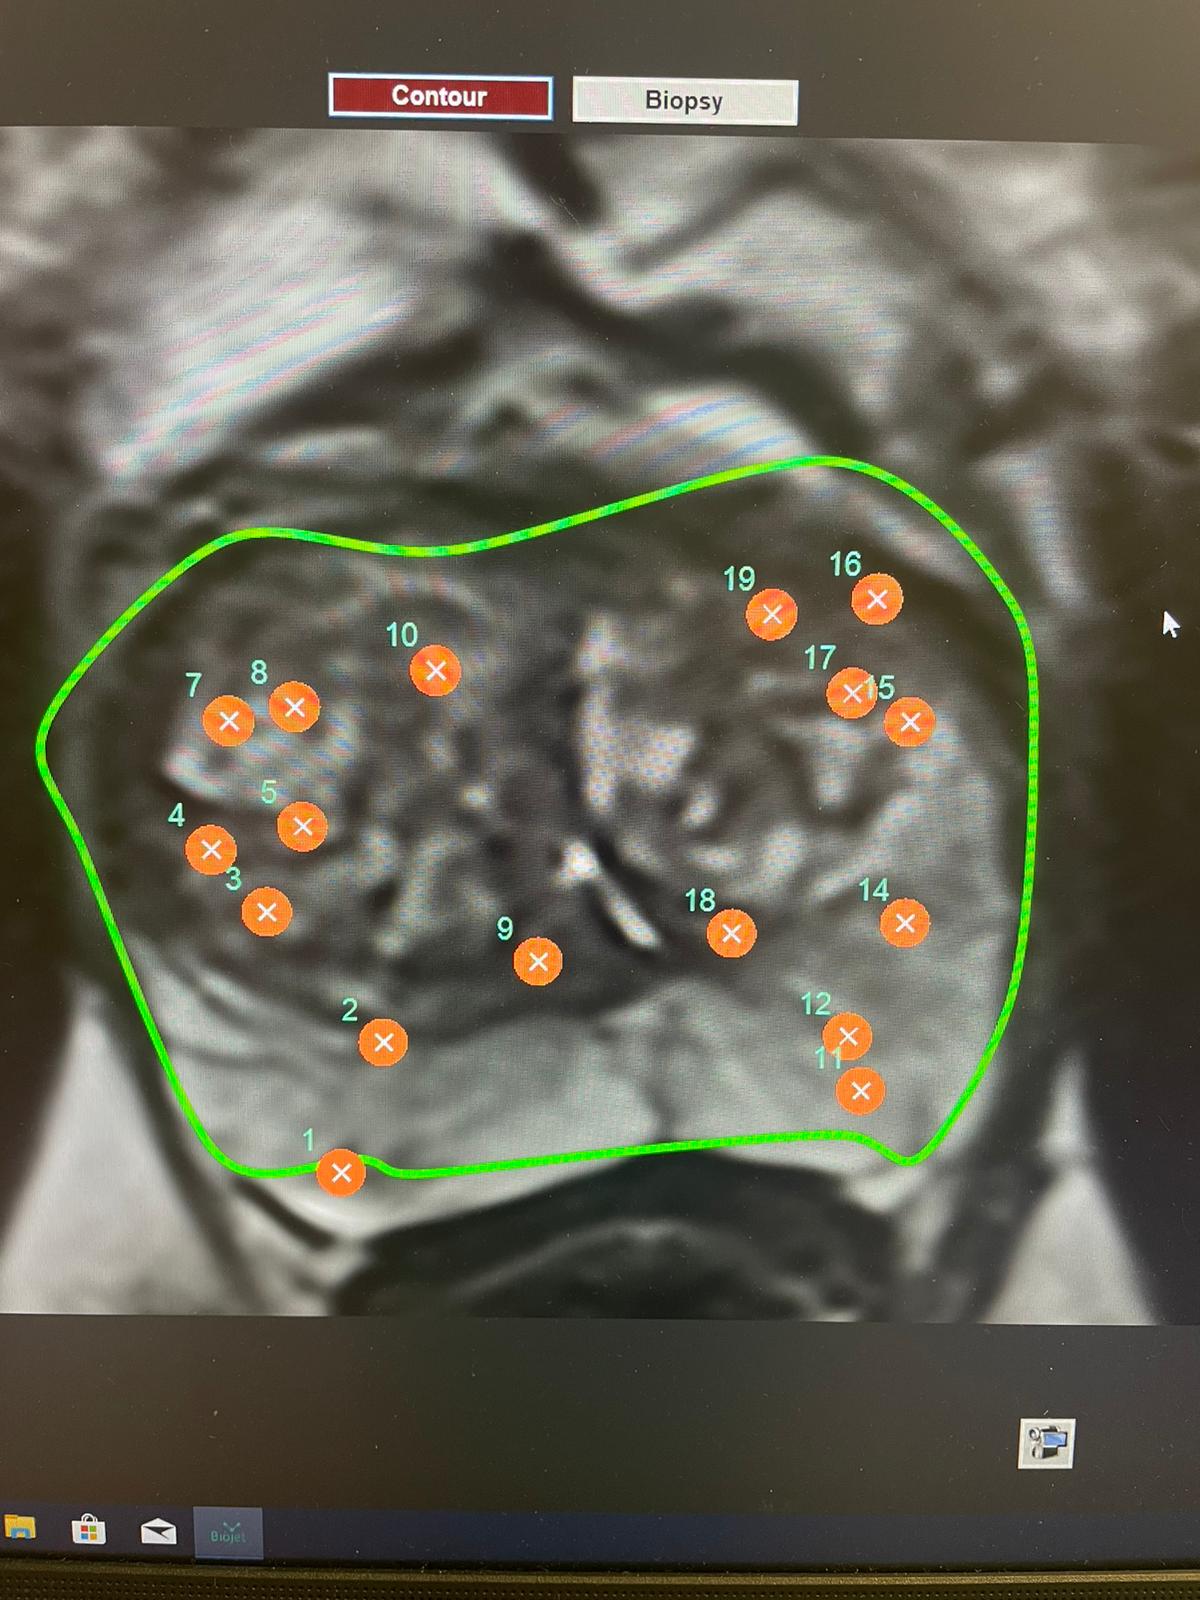

Prostatakrebs zählt zu den häufigsten Krebserkrankungen des Mannes. Standardtherapien wie Operation oder Radiotherapie können den Tumor zwar beseitigen, führen aber nicht selten zu Miktionsbeschwerden oder Erektionsstörungen. Die sogenannte „Fokale Therapie“ verfolgt einen anderen Ansatz: Sie zerstört nur den erkrankten Bereich und belässt den Rest der Prostata unversehrt. Bei der Hochintensitäts-Fokussierten Ultraschalltherapie (HIFU) wird der Tumor mithilfe von Magnetresonanztomografie und Echtzeit-Ultraschall millimetergenau erhitzt und zerstört. Bislang gilt diese Methode laut den Leitlinien der European Association of Urology als experimentell – unter anderem, weil aussagekräftige prospektive Daten fehlten. Die aktuelle Studie der KL Krems und klinischen Partnern in St. Pölten, Baden und Korneuburg liefert die notwendige Evidenz zu diesen Themen.

„Anstatt die gesamte Drüse zu entfernen oder zu bestrahlen, behandeln wir nur den erkrankten Teil – gesteuert durch MRT und Echtzeit-Ultraschall“, erklären OA Dr. Gábor Rosta und Prim. Prof. Dr. Harun Fajkovic von der Klinischen Abteilung für Urologie und Andrologie am Universitätsklinikum St. Pölten, einem Lehr- und Forschungsstandort der KL Krems. „Unsere Ergebnisse zeigen, dass dieser fokussierte Ansatz bei ausgewählten Patienten den Krebs wirkungsvoll kontrollieren und die Nebenwirkungen herkömmlicher Behandlungen signifikant senken kann.“

Im Rahmen der prospektiven Machbarkeitsstudie wurden zwischen 2021 und 2024 insgesamt 51 Männer mit neu diagnostiziertem, lokal begrenztem Prostatakarzinom niedrigen oder mittleren Risikos behandelt (Tumormarker PSA ≤ 15 ng/mL, Stadium ≤ T2). Bei allen wurde die erkrankte Region gezielt mittels MRT-gestütztem HIFU abgetragen. Die Studienteilnehmer wurden über zwei Jahre nachbeobachtet – mit vierteljährlichen PSA-Kontrollen, MRT-Untersuchungen nach 12 und 24 Monaten sowie anschließenden Biopsien.